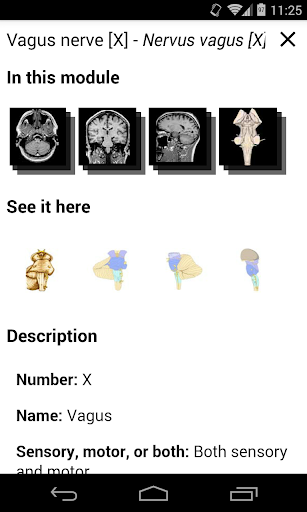

e-Anatomy tiene más de 26 000 imágenes que contienen series de imágenes en vistas axiales, coronales y sagitales, así como radiografías, angiografías, imágenes de disección, gráficos anatómicos e ilustraciones. Todas las imágenes médicas fueron etiquetadas cuidadosamente, más de 967 000 etiquetas disponibles en 12 idiomas, incluida la Terminologia Anatomica latina.

- Toque las etiquetas para mostrar las estructuras anatómicas

*Vista detallada mejorada de partes anatómicas para una identificación más fácil en imágenes del módulo actual y otros.

la vista de detalles de una estructura anatómica ahora se muestran los términos relacionados